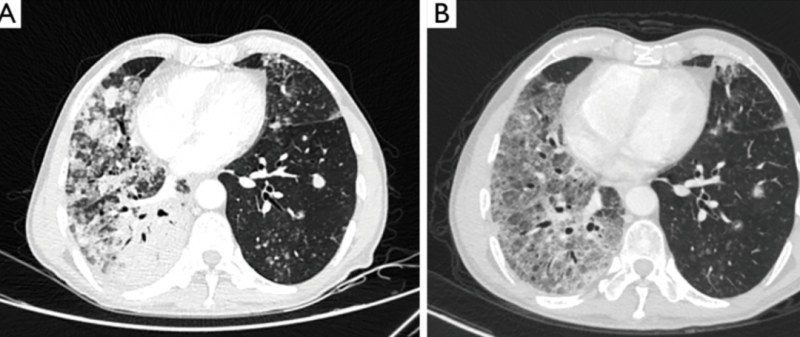

张大爷再一次幸运的参加了伏美替尼的临床试验。让张大爷没想到的是,这款药物的效果比第一次接受的TAK788还要好,仅3个月,他就达到了部分缓解,这意味着他的肿瘤病灶至少缩小了30%!下面这张治疗前后的CT也清晰的展示了病灶的缩小。并且截止到2022年3月文献发表时,张大爷仍在接受治疗,伏美替尼给张大爷带来了持久的缓解,我们也希望张大爷能继续获益于伏美替尼的治疗,也希望一代一代的靶向药能层出不穷,让病友们都能活过5年,10年!